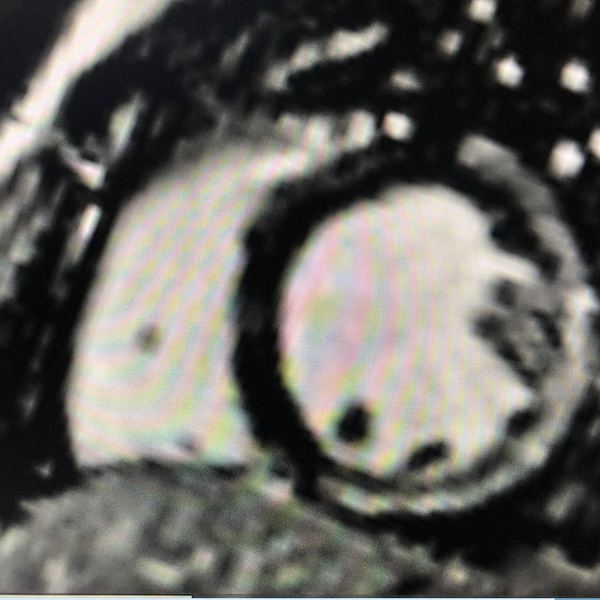

A subendocardial membrane is a distinctive sign of this condition